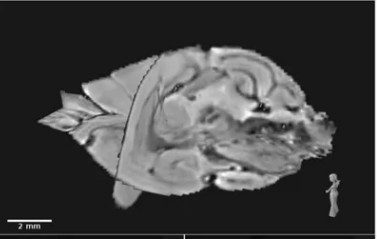

Seasonal brain plasticity, cognition, shrews... explored through data and visual storytelling.